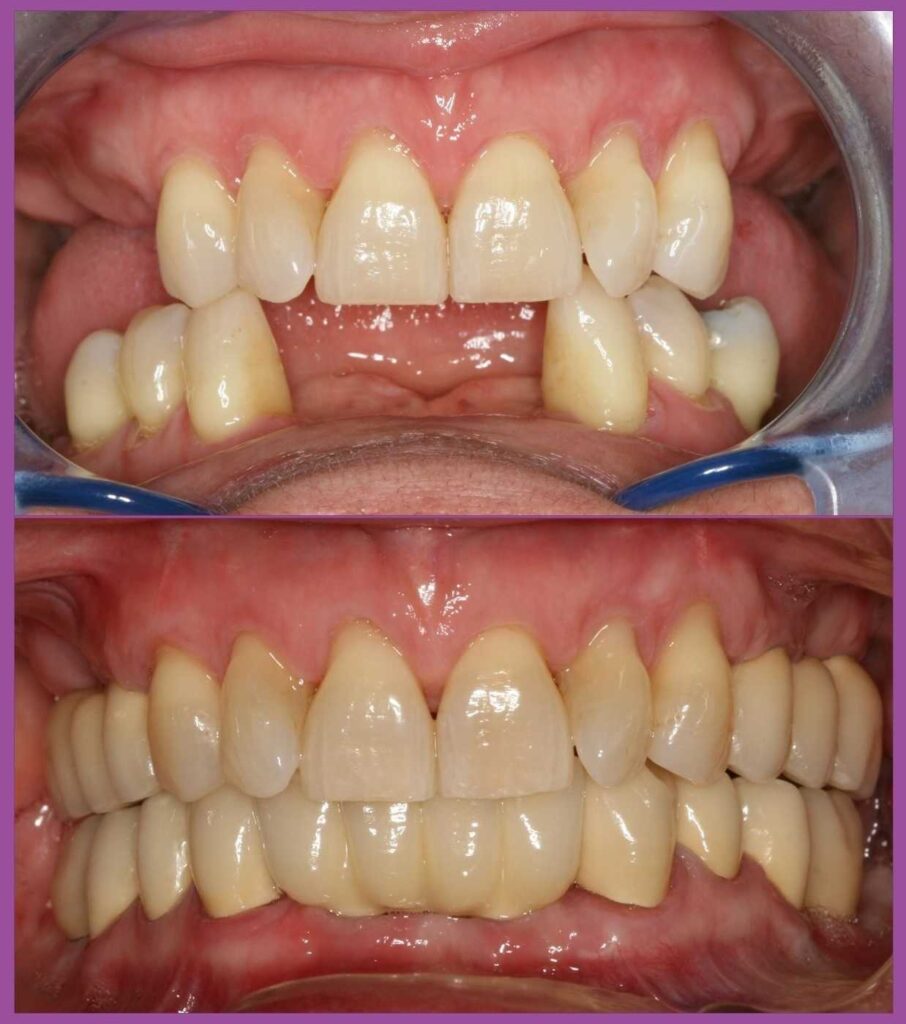

A kezelési terv készítése során fontos szempont volt, hogy a páciens ne maradjon fog nélkül. A menthetetlen fogak eltávolítását megelőzően ideiglenes fogpótlásokat készítettünk a fogtechnikai labor segítségével, és a foghúzásokat követően ezeket egyből meg is kapta a páciens.

Miután sikerült a fogágypusztulást megállítani, és ezt az állapotot stabilizálni, megtörtént a foghiányok végleges pótlása implantátumok és fémkerámia fogpótlások segítségével. Ezalatt a pácienssel és a dentálhigiénikus kolléganővel közösen kialakítottunk egy olyan fogmosási rutint, amellyel a hölgy fenn tudja tartani a gyulladásmentes állapotot.